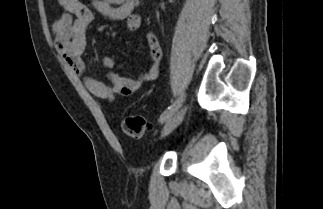

Мультиспиральная компьютерная томография позволяет детально оценить структуру лимфатических узлов, выявить ее неоднородность, определить точные размеры, выявить деформацию контуров, появление инфильтрации окружающих тканей с образованием цепочек, пакетов и конгломератов лимфоузлов.

Мультиспиральная компьютерная томография позволяет оценить структуру лимфатических узлов, обнаружить неоднородность, гиперплазию, деформацию их контуров.

Мультиспиральная компьютерная томография дает возможность визуализировать размеры лимфоузлов, их точную локализацию, взаимодействие с близлежащими органами и окружающими тканями, образование спаянных между собой инфильтратов лимфоузлов, выявить прорастание в окружающие ткани.